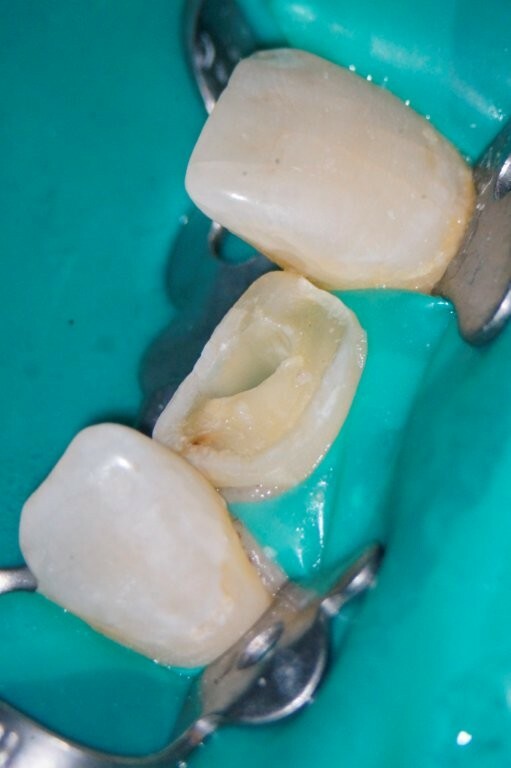

Das Zahnfragment hatte eine gute Passung auf den frakturierten Stumpf. So konnte im Vorfeld ein Silikonabdruck als Vorwall für den Kompositaufbau erstellt werden. Die endodontische Therapie sowie der Füllungsaufbau erfolgten ausschließlich unter dem hochauflösenden OP-Mikroskop (Zumax OMS2350). Die zu behandelnde Region wurde mit Ubistesin 1/200000 lokal betäubt. Anschließend wurde von 11 bis 22 ein Kofferdam angebracht. Der Zahn wurde mit einem konischen Diamanten trepaniert, die Trepanationsöffnung mit Gates-Glidden-Bohrern erweitert. Die Aufbereitung erfolgte mit dem Reciproc Blue System bis zur Größe 50.05.

Guttapercha und AH Plus als Sealer. Anschließend wurden aufgrund der ovalen Kavität zwei Glasfaserstifte zur Stabilisation der Füllung eingebracht und mit Luxacore adhäsiv verklebt.

Der provisorische Aufbau erfolgte durch den Endodontologen mit vorab gefertigtem Silikonschlüssel mittels Tetric Flow und Ceram A3,5 als Abschluss der Single-Visit-Behandlung. Die endgültige Krone konnte am 12. Juni 2025 eingegliedert werden.